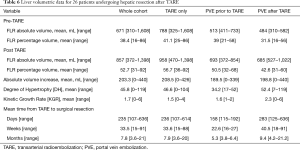

A summary of liver volumetrics is given in Table 6. The mean FLR volume/percentage was 671 mL (310–1,608 mL)/38.4% (16–86%) before TARE and 857 mL (372–1,398 mL)/52.7% (31–92%) after TARE. The mean DH and KGR was 45.8 [0–119] and 1.7 [0–6], respectively.

Full table